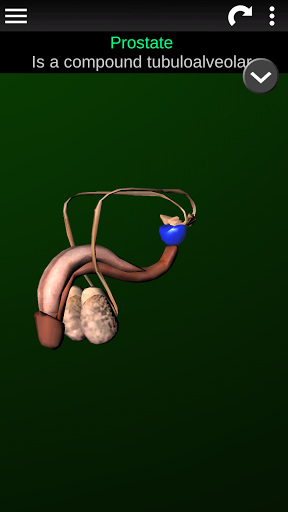

Shows a 3D anatomical model of the main organs of the human body and a description of each one.

* Reproductive system, which includes the male and female reproductive organs.

* Descriptions of each organ.